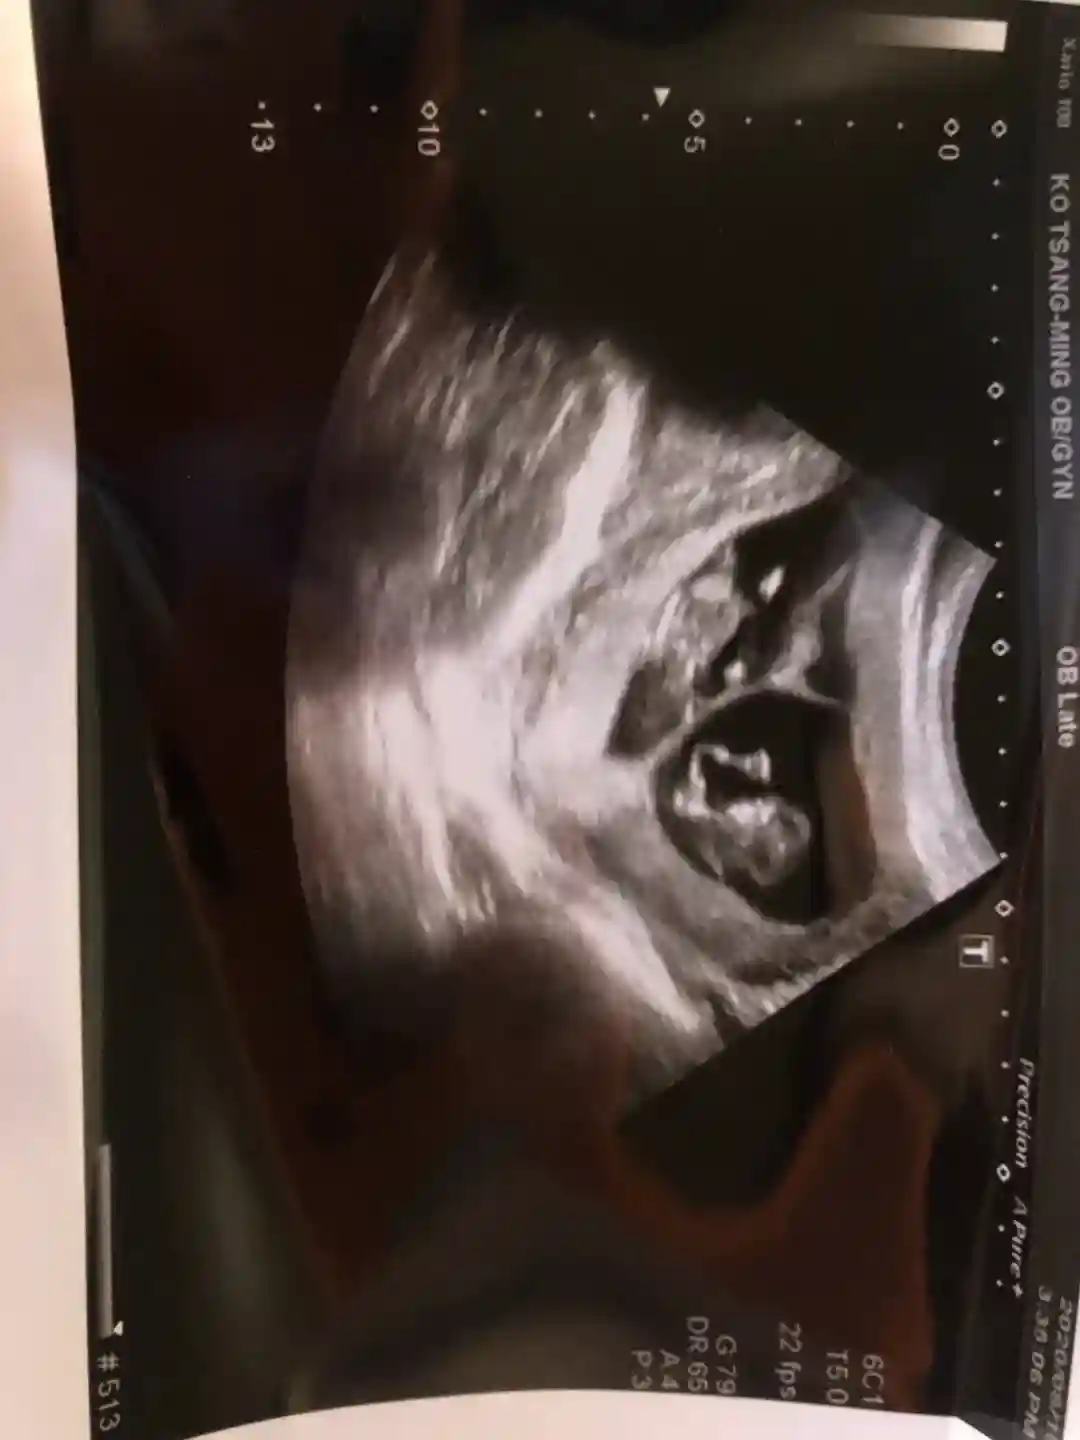

这个针的针头非常的细小,扎其实不太会痛(而且我属于超级无敌怕痛的人,觉得可以接受的),打完这个针1周后要回诊,会照超音波看卵泡发育情况,再继续打普通的排卵针,会给你一个针剂分两次或者三次打,每次固定剂量,大概普通的排卵针会配一到两针,等卵泡发育差不多,会给你一剂破卵针会在他们算好的时间打,打完的隔天会安排去卵手术啦!

手术会全麻,打点滴形式,你会睡着一会,医生在你麻醉状态下进行去卵,很快取完,你没什么感觉,不疼。取完一会麻药过了你也会醒来,就可以换上自己衣服走啦!医生会告诉你一些去卵后的会发生的一些问题,比如头两天阴道可能会有一点出血都正常(我是没有出血)还有就是取的卵子越多,你的腹胀腹部积水越严重,需要补充大量蛋白质,最好喝蛋白粉,反正你会觉得腹部变得鼓鼓的,不停排尿,大概我持续了5天慢慢好转一点点因为我是准备植入冷冻胚胎,所以我不着急移植,我取了28了卵,成功配成了22个胚胎,取得卵子算多,所以腹部积水会比较多,我就让自己休息了两三个月,恢复一下卵巢,这样也会比较容易移植成功,像我腹部积水多,直接移植鲜胚,会容易整个人水肿,并且不利于胚胎着床,所以建议那些去卵多的,别着急,让自己卵巢休息一两个月再移植也没事